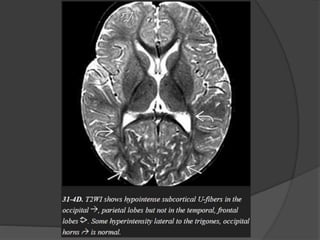

MR findings

A posterior-predominant pattern is seen in 80% of patients with X-

ALD.

The earliest finding is T2/FLAIR hyperintensity in the middle of

the corpus callosum splenium.

As the disease progresses, hyperintensity spreads from posterior

to anterior and from the center to the periphery.

The peritrigonal WM, corticospinal tracts, fornix, commissural

fibers, plus the visual and auditory pathways can all eventually

become involved.

MR findings A posterior-predominantpattern is seen in 80% of patients with X- ALD. The earliest finding is T2/FLAIR hyperintensity in the middle of the corpus callosum splenium. As the disease progresses, hyperintensity spreads from posterior to anterior and from the center to the periphery. The peritrigonal WM, corticospinal tracts, fornix, commissural fibers, plus the visual and auditory pathways can all eventually become involved.